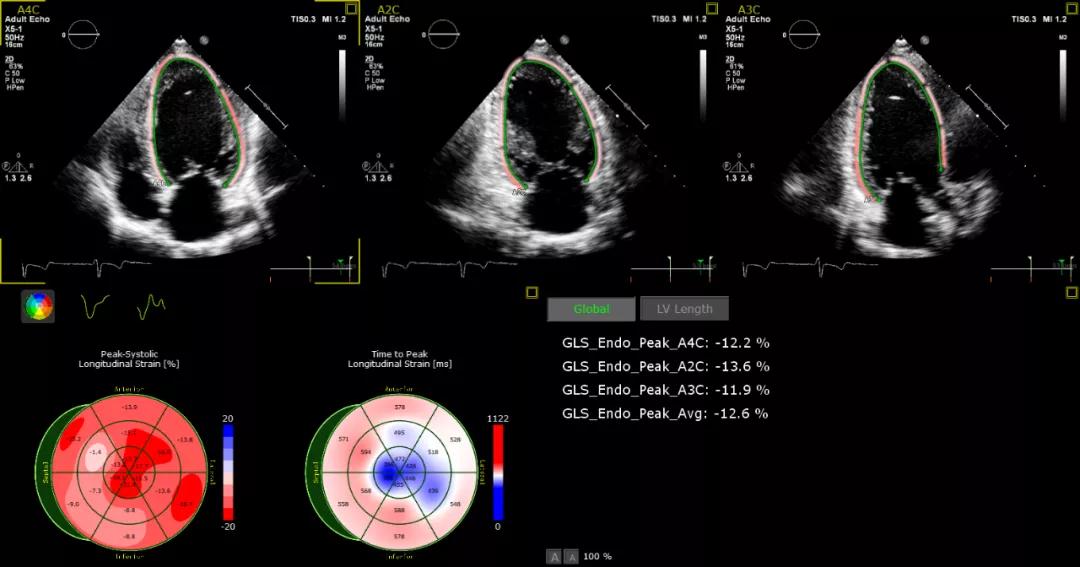

全新的心功能定量技术也对介入医生有着很大的帮助:“这台新的超声系统融入了AI元素,不仅可以帮助医生加深理解心脏结构和毗邻关系,还能快速评估心功能各项指标,如左心室、左心房等心腔的功能。以往医生对患者病情判断偏重于对心脏腔室关系的评估,现在新增了心脏功能的评估,将使得治疗更精准。”